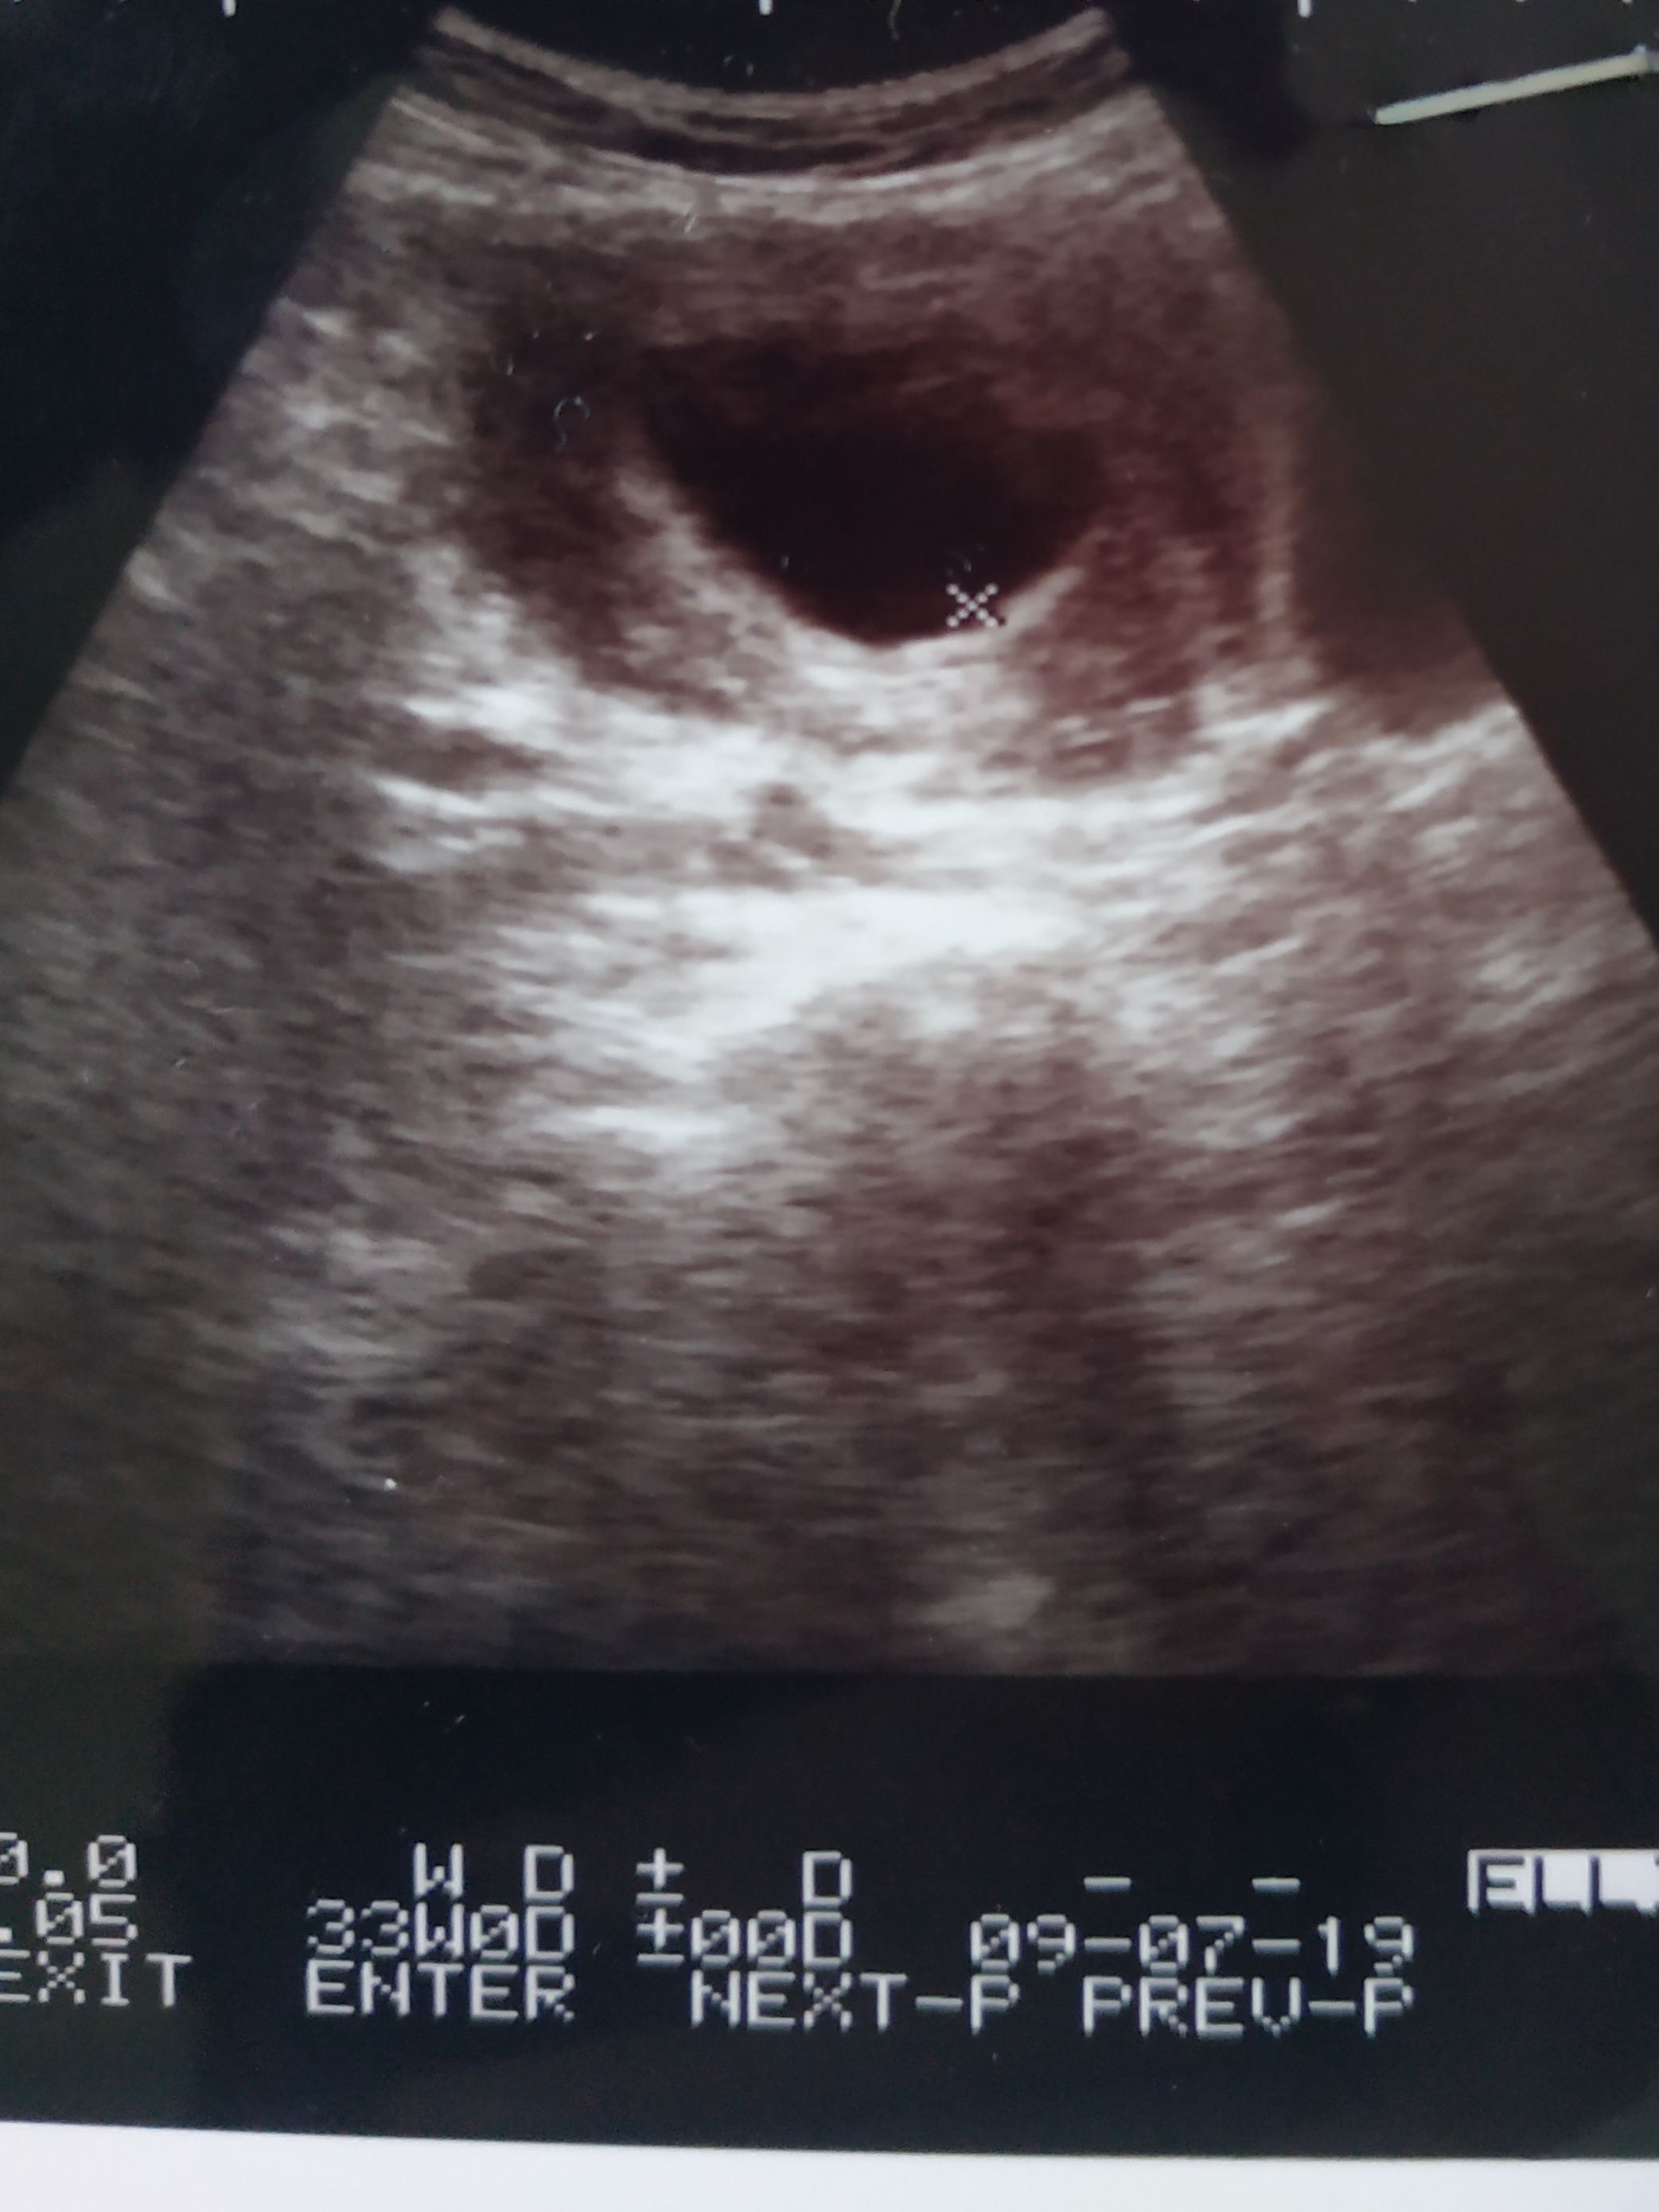

Blighted ovum with twins

A blighted ovum may also occur in a twin pregnancy. In this instance, it is called a blighted twin, one of the fertilised eggs fails to develop properly while the second develops normally, completely unaffected by the blighted twin.

This type of miscarriage is usually diagnosed using ultrasound that can be usually done on the 8th week of pregnancy. It will show a large gestational sac, but no embryo. Many doctors use the term “early pregnancy failure,” instead of “blighted ovum” to describe this common type of miscarriage that accounts for approximately 50 percent of first trimester miscarriages.

The Criteria For A Diagnosis Of Blighted Ovum Are:

- Failure to identify an embryo in a gestational sac measuring at least 20 mm via transabdominal ultrasound.

- Failure to identify an embryo in a gestational sac measuring approximately 18mm or more via transvaginal ultrasound.

- Failure to identify a yolk sac in a gestational sac measuring 13mm or more.